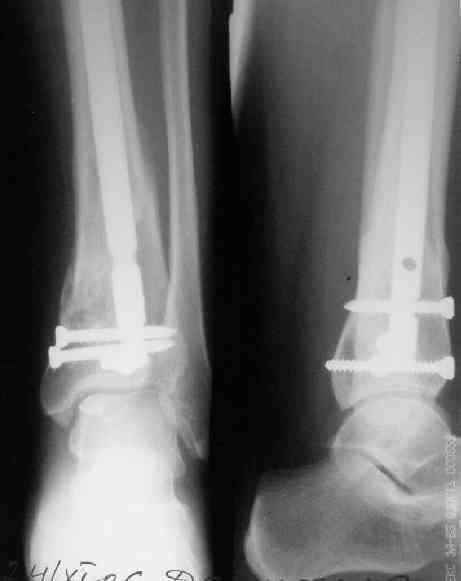

В приложении пример лечения аналогичного повреждения (плюс задний край).

> В приложении пример лечения аналогичного повреждения (плюс задний край).

Превосходно!